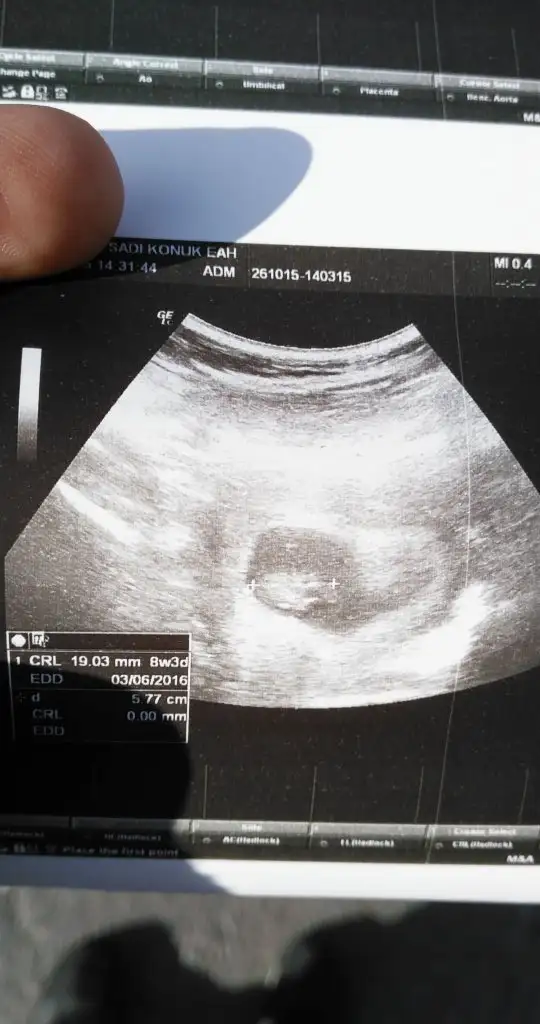

En son geçen çarsamba duydum kalp atısıni. O zaman doktor 8+0 demisti. Suanda da 8+6 yarin 9 olacak insaallahmerhaba benimde sat 26 ağustos döngülerim genelde 30-35 gün arası oluyor 6 ekimde hamile olduğumu öğrendim. 2 hafta önce keseyi gördük 22 mm di. en son 24 ekim cumartesi kalp atımını duyduk ancak çok net değildi. ama çizelgede attığını ve yeni oluştuğunu söyledi. doktor bu hafta gel daha net duyarız ondan dsonra artık 1 ay sonra çağırıcam seni dedi. :) sizinle satımız aynı olduğu için yazmak istedim. Şuan kaç haftalık görünüyor ultrasona göre ?fbtl

Maşallah harikaMerhaba herkese. Herkes iyidir umarım bir süredir bu sayfayı okumadım. Bebişler iyidir inşallah. Size güzel haberler vereyim. Bugün doktor kontrolümüz vardı. Bebişimiz çok iyimiş maşşallah 2.14 cm olmuş harekette etti çok güzeldiDoktor 8+5 haftalık uyumlu gidiyor çok güzel dedi. herşey yolunda çok şükür. 11. haftada gidicez tekrar ben bi erkenden ense kalınlığına bakayım dedim. 12-13. haftada 2 li yani zeka testi yaptıracaksın iyi çıkarsa 3 lü ye 4 lüye gerek kalmayacak, 20. haftadada ayrıntılı usg yaptırıp yolumuza devam edicez başka bişey yok dedi. Birde dvd verdi videosu var eve geldim izledim bebişimi. Her gittiğimde götürücem cd yi üstüne kaydedicek çok güzel bir hatıra annemede izlettim hemen :) Doktorum sağolsun iyi ki tanımışım bulmuşum çok güvenilir ellerdeyim ve çok sıcak kanlı aşırı ilgili. Allah sağlıkla kucağımıza almayı nasip etsin inşallah. İyi olduğunu öğrenince çok rahatlıyor insan

Gozunaydn canmm cok sevndm bende dun gordum 2cm di senkinin arkasindym zaten ben resim koydum gordnmu neresi basi flan anlayamadm sen daha detayli farketmmissn banada solermisn bakip:)Merhaba herkese. Herkes iyidir umarım bir süredir bu sayfayı okumadım. Bebişler iyidir inşallah. Size güzel haberler vereyim. Bugün doktor kontrolümüz vardı. Bebişimiz çok iyimiş maşşallah 2.14 cm olmuş harekette etti çok güzeldiDoktor 8+5 haftalık uyumlu gidiyor çok güzel dedi. herşey yolunda çok şükür. 11. haftada gidicez tekrar ben bi erkenden ense kalınlığına bakayım dedim. 12-13. haftada 2 li yani zeka testi yaptıracaksın iyi çıkarsa 3 lü ye 4 lüye gerek kalmayacak, 20. haftadada ayrıntılı usg yaptırıp yolumuza devam edicez başka bişey yok dedi. Birde dvd verdi videosu var eve geldim izledim bebişimi. Her gittiğimde götürücem cd yi üstüne kaydedicek çok güzel bir hatıra annemede izlettim hemen :) Doktorum sağolsun iyi ki tanımışım bulmuşum çok güvenilir ellerdeyim ve çok sıcak kanlı aşırı ilgili. Allah sağlıkla kucağımıza almayı nasip etsin inşallah. İyi olduğunu öğrenince çok rahatlıyor insan

Öylemi diyosun canım yacnm heyecan yapma ben 19,1 mm de keseyi gördüm 1 hafta sonra kesem 22,2 mmdi kalp atışını daha doğrusu ritmini gösterrdi doktor.daha yeni oluşuyor 1 hafta sonra gümbür gümbür duyulacak sesi demişti.Bu hafta kısmetse duymaya gideceğiz..oyüzden kesenin büyük olmasından korkma küçükse şayet bekle büyüyecektir.